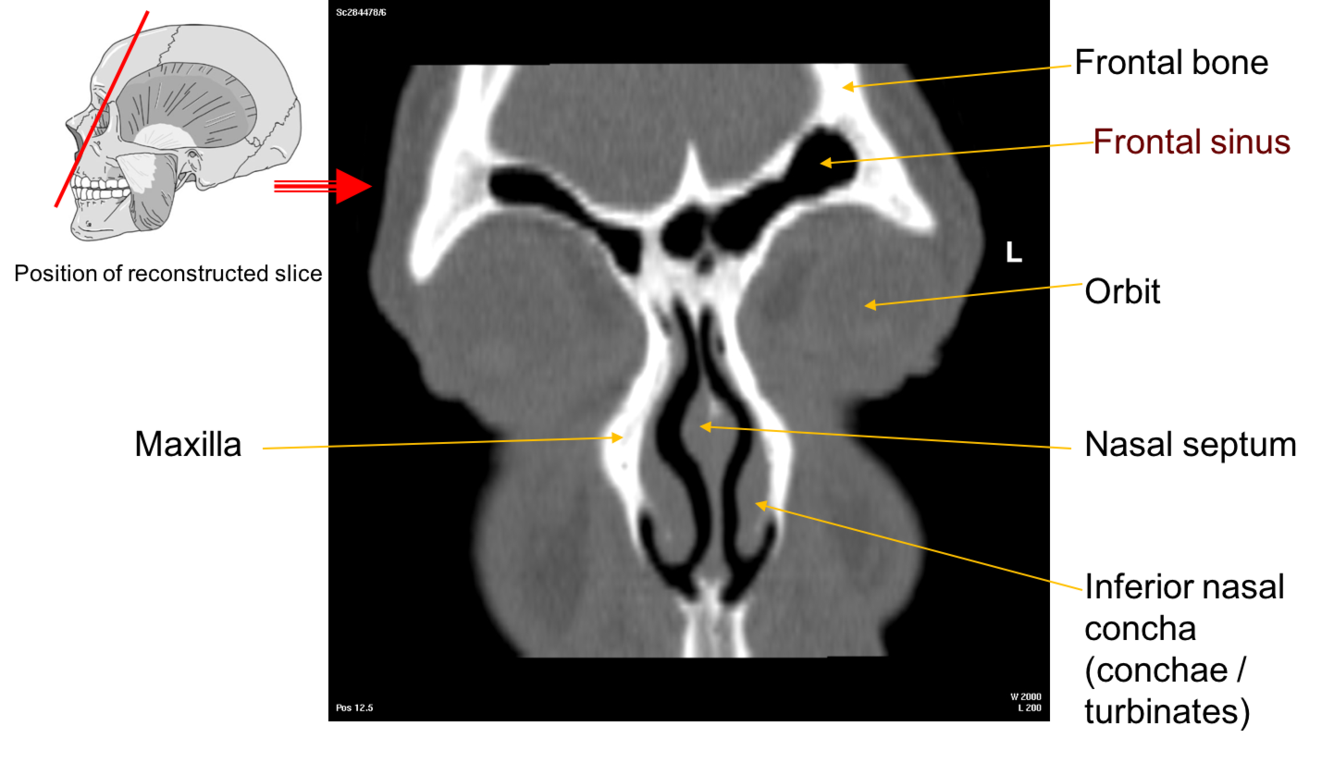

Label this image

The Nasal Conchae also called turbinates

These are thin scroll shaped bony plates that project into the nasal cavity. There are usually three the superior, middle and inferior nasal conchae (supreme may also be present).

•These conchae form passageways – the superior, middle and inferior meatae which are lined by mucous membrane

•This arrangement increases the surface area of the nasal cavities providing for rapid warming and humidification of air as it passes to the lungs.